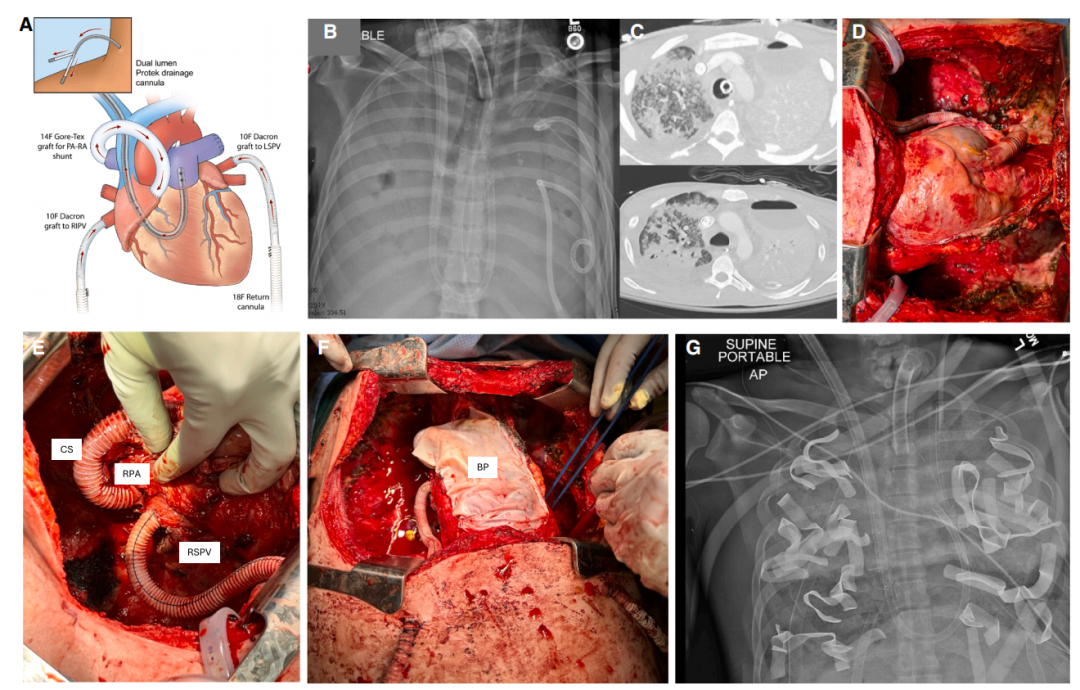

这群医生做了一个从未有过的手术。手术团队先切开了男子的胸腔,用的是双侧乳房下切口加胸骨横断的蛤壳式开胸。他们用 31F 的双腔插管从颈内静脉穿到肺动脉,一根管同时引流右心房和肺动脉的血,最高流量能超过 8 升每分钟。

肺切除之后,肺血管床没了,右心室射出的血没了缓冲池,可能瞬间胀破肺动脉残端。医生们想了一个巧妙的办法,用 14 毫米的人工血管在右肺动脉和右心房之间搭了一个电容分流管。

这个分流管的原理很简单,当右心室泵出的血超过引流泵抽走的能力时,多余的血液会自动经分流管回流右心房,压力一平衡就停止。术中测试显示,这个分流管的流量在 1.1 到 6.3 升每分钟之间自动调节。

为了维持左心室充盈,医生们需要把氧合好的血送回心脏。他们把两根 10 毫米的人工血管缝在左右上肺静脉上,直接把血送回左心房。

之所以用两根是为了保持冗余,万一其中一根堵了,可以随时切换另一根,不会中断血流。心包则使用牛心包重建,以便防止心脏在空的胸腔里晃动。胸腔里塞满了盐水扩张器和手术巾,以便防止心脏移位和管道打折。